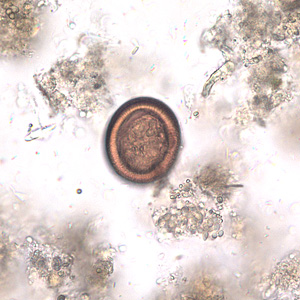

2014年04月08日、愛知県阿久比町の山中で捕獲された犬の糞から寄生虫「エキノコックス」の卵が見つかり、さらなる「南下」も危惧されている。ここではエキノコックス症の基本情報についてまとめてみた。

人が感染すると重い肝障害を起こす寄生虫

人が感染すると重い肝障害を起こす寄生虫エキノコックスが本州に拡大する兆候が出ている。エキノコックスの流行は国内ではキツネが多い北海道だけと考えられてきたが、道外でも感染の報告が続き、4月には愛知県で